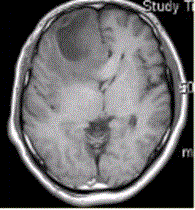

问题 患者女,67岁,头痛伴呕吐1周。既往体健。MR表现如下图。 关于多形性成胶质细胞瘤,描述正确的是

选项 A.儿童青少年常见 B.好发于额、颞叶大脑灰质及白质区 C.CT平扫密度均匀 D.增强检查均匀强化 E.瘤周水肿轻微,占位效应显著

答案 B